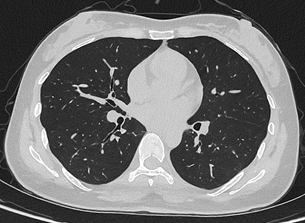

目前,华西厦门医院已基于该设备完成第一批患者扫描。“光子计数能谱CT的临床落地,是我国创新能力的重要体现,真正实现了对国外 ‘卡脖子’技术的突破。光子计数能谱CT实现了降低辐射剂量,让患者CT扫描更安全。我们在临床案例中看到,设备不仅低剂量且高清,肺结节依然清晰可辨,临床价值十分突出。设备将在华西厦门医院的全链条、全生命周期的健康管理服务中发挥重要作用。” 华西厦门医院党委书记廖志林说。

联影uCT Ultima扫描的0.2mm肺部超高清成像,扫描剂量低至0.1mSv联影uCT Ultima扫描的0.2mm肺部超高清成像,扫描剂量低至0.1mSv